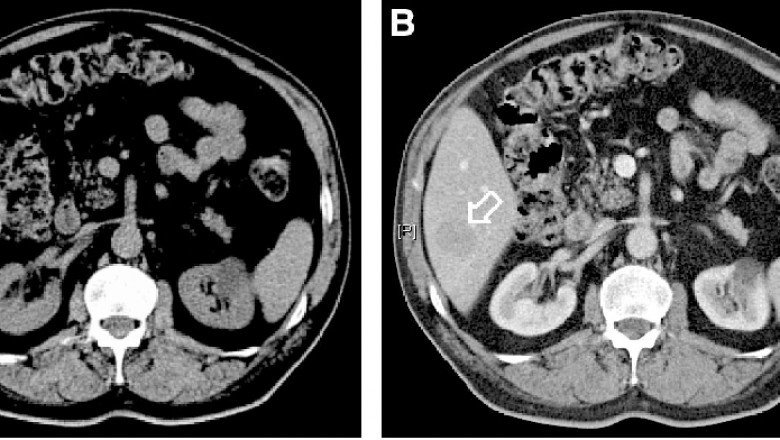

Barium sulphate is the opaque medium that is most frequently utilised. From Contrast Media/Contrast Agent insoluble heavy metal salt is mixed with water and typically given as a barium enema to check the rectum, colon, and terminal ileum. The patient's oesophagus and stomach are also examined using this method. The spleen, liver, bile ducts, blood arteries, gallbladder, and urinary system are all examined with iodized organic substances. The insertion of unsaturated vegetable oil partially saturated with iodine into the bronchial tree allows for greater X-ray vision of the bronchi than that obtained just by the contrast of confined air. The investigation of the spinal canal and bronchography both use an emulsion of ethyl iodophenylundecylate (myelography)